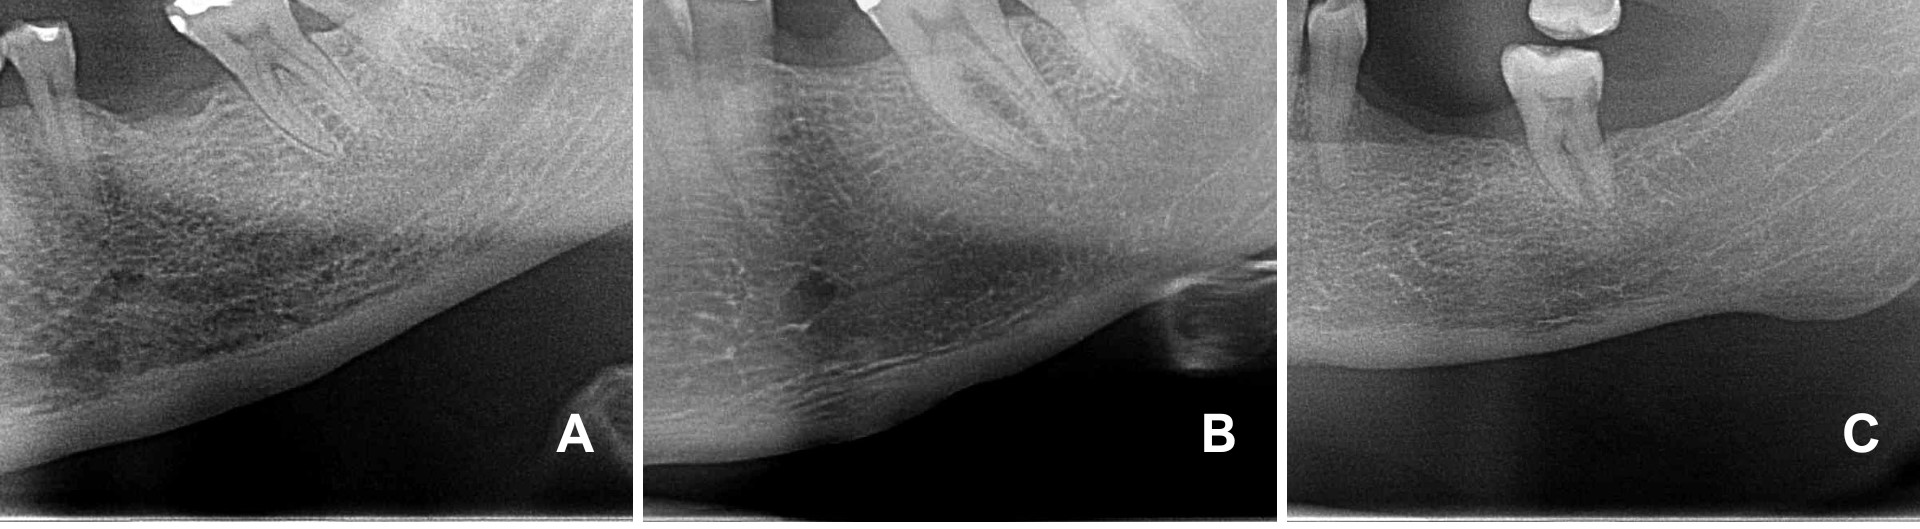

The images were analyzed in a blinded manner by six observers with expertise in Oral and Maxillofacial Radiology. The visibility of specific anatomical structures in the craniofacial region, including the mandibular canals, mental foramina, and cortical bones of the maxillary sinuses, was evaluated on both sides. Visibility was categorized as fully visible, partially visible, or not visible (Figure 1).

Figure 1: Visibility of the mental foramen and mandibular canal. A) not visible; B) partially visible; C) fully visible. View Figure 1